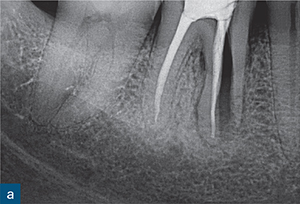

수직치근파절(VRF, Vertical Root Fracture)의 모습입니다. 진한 흰색으로 되어있는 부분이 신경치료가 된 부분인데요, 왼쪽 뿌리와는 달리 오른쪽 뿌리는 파절이 되어있는걸 보실 수 있습니다(출처: https://pocketdentistry.com/vertical-root-fractures/)

겉으로는 거의 멀쩡해 보여도

치아 뿌리에 세로로 파절(vertical fracture)이 생긴 경우가 있습니다.

이걸 수직치근파절(VRF, Vertical Root Fracture)이라고 부르는데요.

씹을 때만 아프고

힘을 빼면 괜찮아지는 특징 😖

X-ray에 잘 안 보이기도 함

이 경우 발치가 필요한 상황으로 이어질 수 있습니다 ⚠️

겉으로 보이는 크기가 아니라, ‘균열의 방향과 깊이’가 핵심입니다.